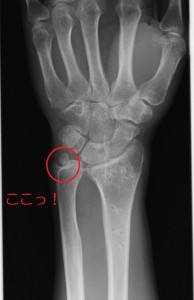

自動車搭乗中、交差点内で右折待ち中、前方から飲酒運転の車が右折専用レーンを直進してきたため、正面から衝突を受ける。骨折した手関節を主訴に後遺障害申請をするも、結果は非該当であった。

【問題点】

相談に来られた時点で受傷から1年以上経過しており、病院にも5ヶ月以上行っていなかった。他にも多数骨折していたが、後遺障害の対象部位は手関節のみ、しかし、時間の経過と共に可動域制限は回復していた。  20141203_2 【立証ポイント】

まず、手首のCT撮影依頼。Drも協力的であり、快諾。CT画像から茎状突起と月状骨から遊離骨片がみられた。橈骨茎状突起の変形と疼痛の残存を理由に12級8号、あるいは13号を目指した。しかし、遊離骨片程度での変形狙いに調査事務所の怒りを買ったのか、1か月もしないうちに非該当の通知が来る。しかも神経症状(12級13号)の認定すらない。このような大怪我で非該当は納得がいかないため、異議申立をすることになった。Drに事情を説明し、再度書類を依頼。異議申立は長管骨の変形よりも、痛みの残存を主訴に立証を固めた。

申請をすると今回も1ヶ月も経たないうちに12級13号が認定される。まるで自賠責調査事務所はミスジャッジを認めたかのよう。審査には最低でも3ヶ月はかかると依頼者に説明していたので、このスピード認定には依頼者も驚いていた。本件のMVPは患者想いのDrである。